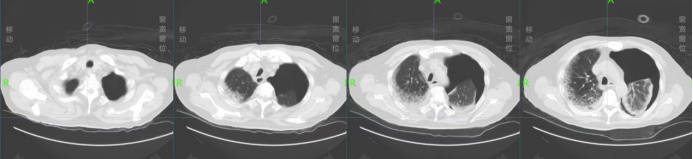

入院后给予鼻导管吸氧,抗病毒、抗炎(口服头孢克洛缓释片)、止咳化痰等治疗。并给予阿司匹林、阿托伐他汀、酒石酸美托洛尔、单硝酸异山梨酯片,控制血糖等基础病支持治疗。患者症状不见好转,于11月20日因患者诉气短、心慌加重,给予面罩吸氧,氧气4 L/min,氧饱和度87%,心率105次/min。11月21日复查胸部CT提示双肺多发磨玻璃影、絮片影,考虑炎性病变,病毒性肺炎,较前进展(图2)

图2  2022年11月21日胸部CT